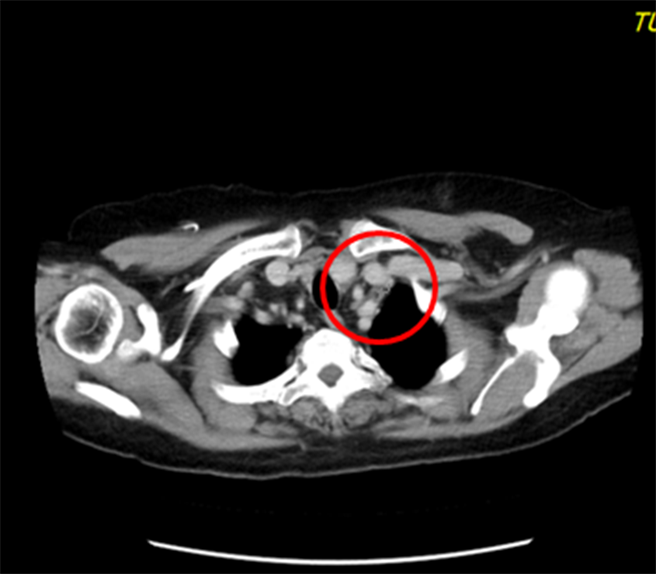

治疗前,颈部肿瘤5x3公分。(童综合医院提供/陈淑娥台中传真)